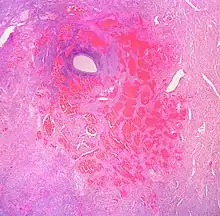

Гемангио́ма (от греч. haima — кровь + angeion — сосуд + -oma) — доброкачественная опухоль, состоящая из самостоятельно инволюционирующих эндотелиальных клеток кровеносных сосудов[2].

По классификации Международного общества по изучению сосудистых аномалий (International Society for the Study Vascular Malformation — ISSVA) 2018 года гемангиомы относятся к сосудистым опухолям и делятся на[3][4]:

- синусоидальную.